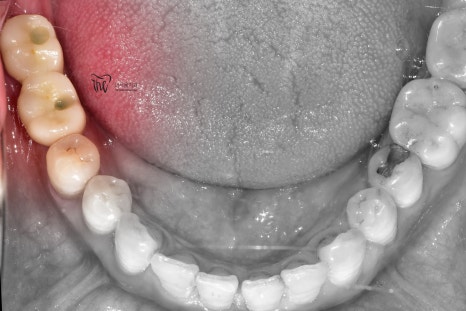

이제, 구강 내 사진에서 보실 수 있는 것 처럼

어금니 빠짐 자리에 새로운 크라운이 자리를

잡으면서 이제 구강 내에 빈 곳이 없어졌네요.

이전처럼, 다시 고기를 맛있게 드실 수 있지

않을까…^^ 그러면서, 현재는 3개월에 한번씩